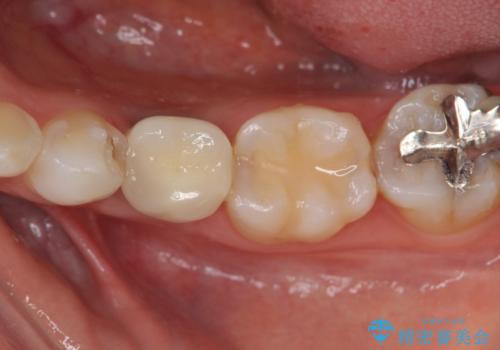

- 大人になっても残存していた乳歯がグラグラし、痛くて噛めない 抜いて欲しいとの希望で来院されました。

歯根が吸収し残すことのできない乳歯を抜去後、隣の歯を削らずに済むインプラント治療で咬合機能の回復を計画します。

乳歯の抜去後、インプラントを用いてしっかりと咬合機能を回復することができました。